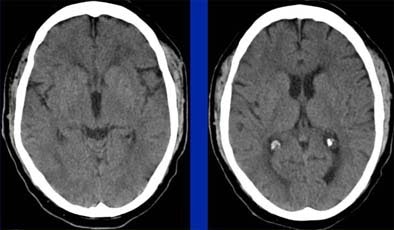

| In an elderly male patient, parametric color maps from perfusion CT show dramatic ischemia in the left hemisphere. In the area of the box, cerebral blood flow (CBF) is decreased (> 34%), cerebral blood volume (CBV) is increased (> 2.5 mL per 100 g of brain tissue), explaining the long mean transit time (MTT), and indicating potentially salvageable brain tissue. However, in the region below the box, substantial matching of blue areas (CBF and CBV) indicates infarcted tissue that is not salvageable. Images courtesy of Dr. Jay Cinnamon. |